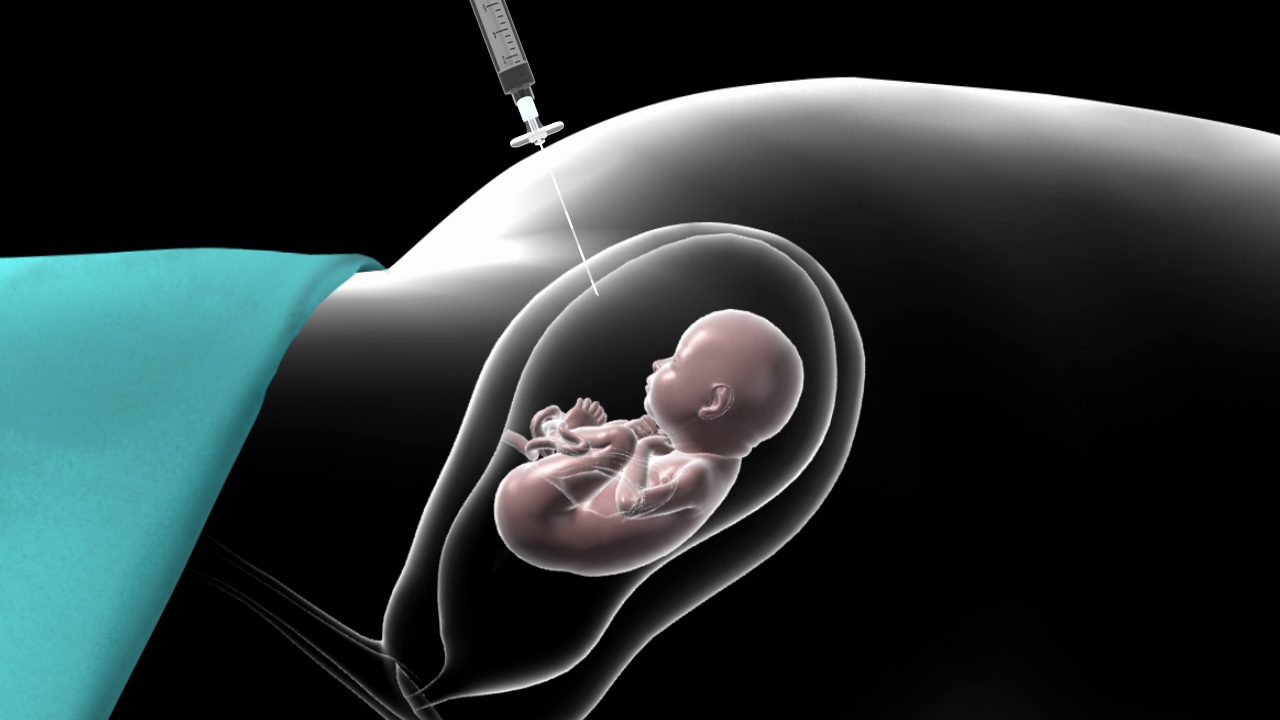

Prenatal Invasive Tests

Explore the deepest insights into your baby's health and genetic profile with our cutting-edge Prenatal Invasive Tests, empowering informed decisions for your family's future.